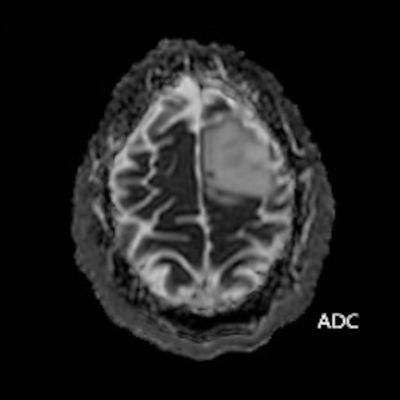

- ADC görüntülerde lezyonda sinyal artışları ile karakterize difüzyon artışı (ok) izleniyor. Bu alana yönelik yapılan multivoksel MR spektroskopi incelemesinde (ok) kolin pikinde artış ve NAA pikinde azalma izleniyor. Cho/Cr oranı 1.76 ölçülüyor.

- DAG’de düşük ADC değerleri varsa bu daha yüksek mitotik aktiviteyi gösterebilir (grade 3–4).